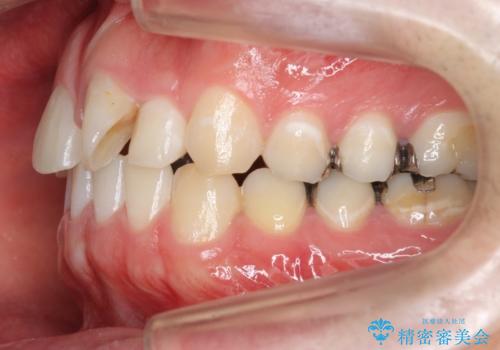

前歯のねじれ 上だけ部分矯正でコストダウン

- 前歯のねじれを部分矯正で治療しました。

奥歯のかみ合わせを変えずに、費用を抑えて短期間に治療したい方におすすめです。

矯正前に、後戻り防止のため上唇小帯の処置を行っています。

奥歯のかみあわせも問題なく、また、下の前歯のがたつきが元からない場合は上の部分矯正が十分可能です。